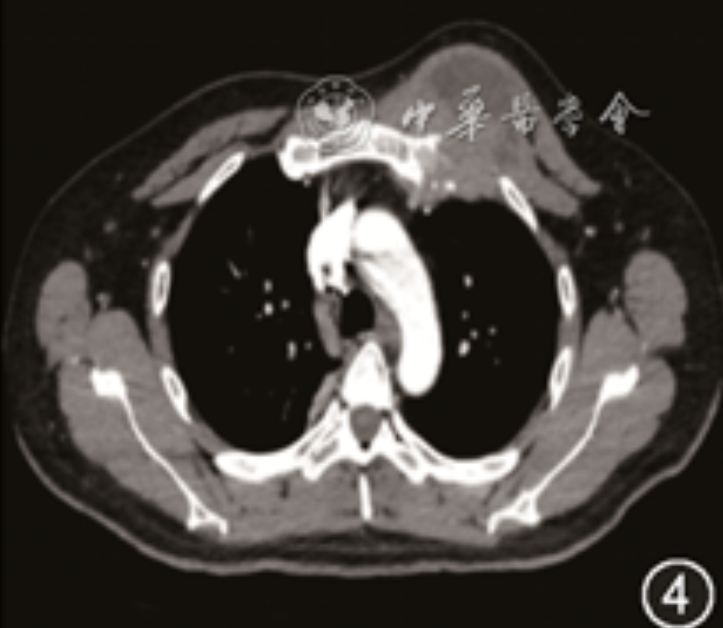

胸部CT(图4, 5, 6):纵隔及右肺门、双侧胸前壁及后腹壁多发囊实性占位性病变,右侧肩胛骨及双侧局部肋骨骨质破坏;头颅CT(图7,8):左顶骨骨质破坏,周围见囊实性软组织肿块,增强扫描后实性成分呈中度强化,囊性成分未见强化。后行超声引导下头部及背部肿物穿刺术,组织病理示(图9):化脓性肉芽肿炎,可见较多多核巨细胞,内可见囊泡状孢子样物,特殊染色结果 PAS(+),六胺银(+);同时将外院右肺下叶切除肺组织送我院病理科会诊,结果示(图10):化脓性肉芽肿性炎,可见大量多核巨细胞,内可见囊泡状孢子样物,特殊染色结果 PAS(+),六胺银(+),考虑为真菌感染,但穿刺组织培养结果阴性,遂行穿刺组织宏基因组二代测序(metagenomics next generation sequencing,mNGS),结果显示:芽生菌属真菌(Blastomyces_percursus,序列数192 870)。

图4 2024年6月8日入院后胸部CT示左胸壁肿物;图5 2024年6月8日入院后胸部CT示肋骨破坏;图6 2024年6月8日入院后胸部CT示后背皮下肿物